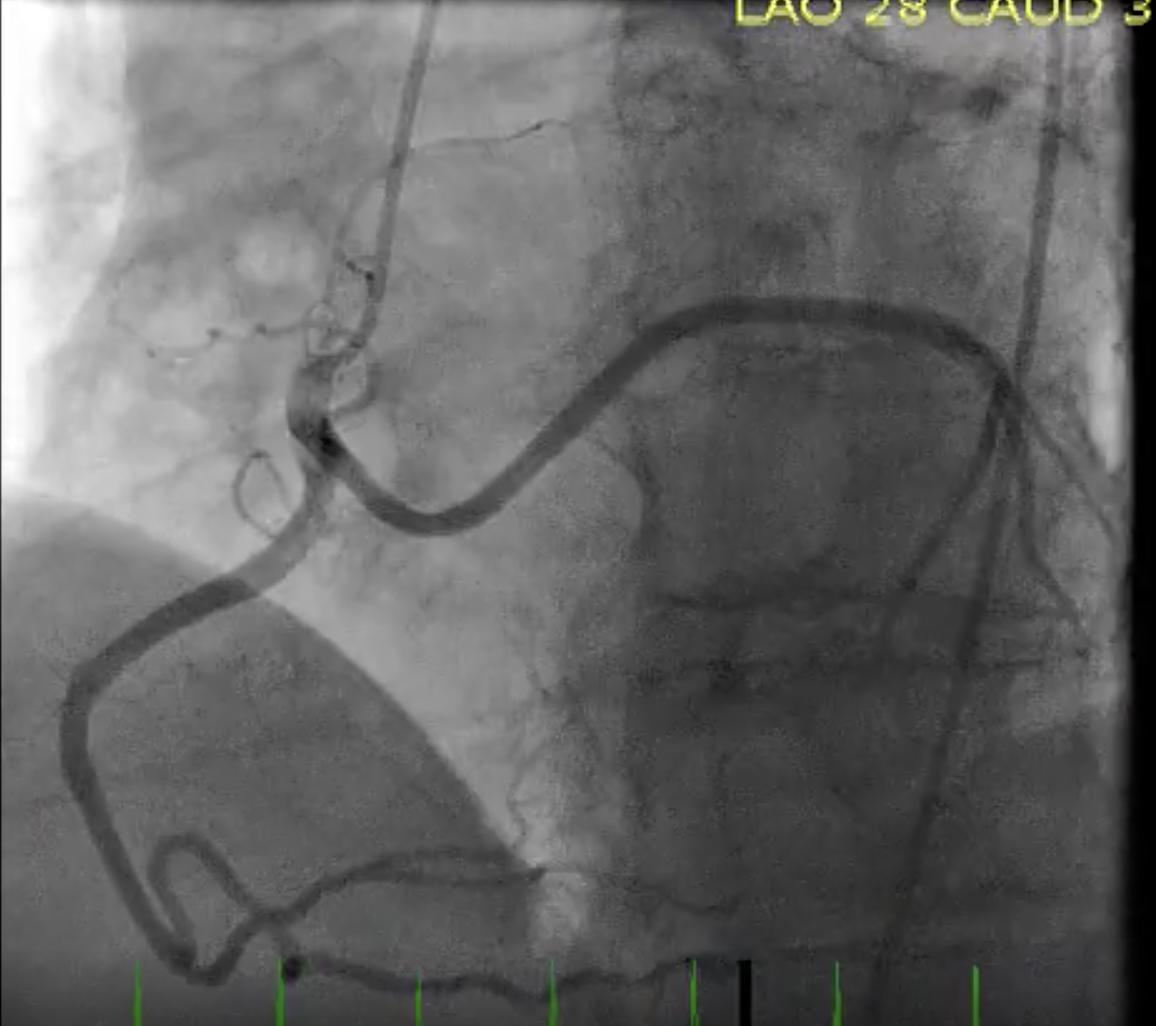

Describe the findings:

RCA dissection